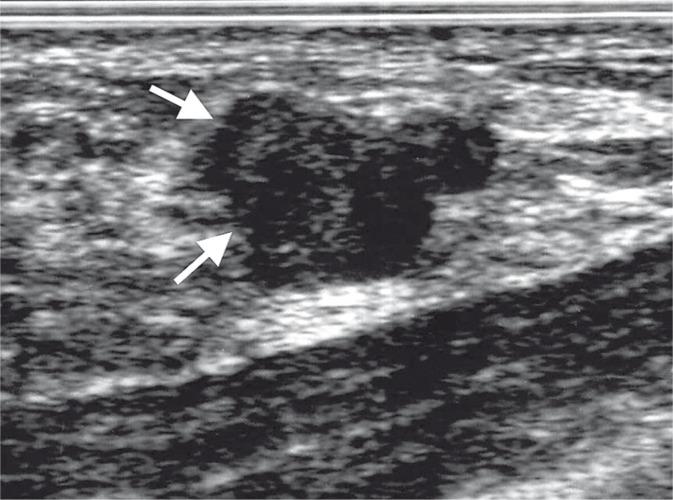

The use of BIRADS classification has been recommended in sonomammography examinations in Poland since the year 2010. It was developed by the Polish Ultrasound Society and published in Ultrasound Examinations Standards of the Polish Ultrasound Society. Standards, based on BIRADS-usg classification, introduced uniformity in breast ultrasound examination descriptions and in the terminology of pathological lesions in breasts. BIRADS-usg classification takes into account breast morphological structure elements and pathological focal lesions in them. It enables the distinction between benign lesions and lesions suspected of being malignant. It contains information on the malignancy risk of focal lesions and proposals of diagnostic-therapeutic algorithms (including biopsy) in relation to lesions of different character. The Polish Ultrasound Society recommends performing prophylactic sonomammography examinations every 12 months in women over the age of 30 because of the increasing breast cancer morbidity in women from all age groups. In this article a spectrum of focal changes in breasts are presented within the relevant BIRADS-usg classification categories. The features of ultrasound morphology, enabling them to be classified to particular categories of BIRADS-usg classification are discussed. Management algorithms which may help clinicians to diagnose breast cancer and to treat it are proposed. Elements of medical history, physical examination, recommended techniques of sonomammography examination performance, technical parameters of ultrasound machine and examination description standards are presented. This article was prepared based on the Ultrasound Examination Standards of the Polish Ultrasound Society which was published in 2011 and updated. It contains numerous pictures visualizing BIRADS-usg classification.

自2010年起,波兰就建议在乳腺超声检查中使用BIRADS分类。它由波兰超声学会制定,并发表于《波兰超声学会超声检查标准》中。基于BIRADS-usg分类的标准在乳腺超声检查描述以及乳腺病理病变术语方面引入了一致性。BIRADS-usg分类考虑了乳腺的形态结构要素及其病理局灶性病变。它能够区分良性病变和疑似恶性病变。它包含有关局灶性病变恶性风险的信息以及针对不同性质病变的诊断-治疗算法(包括活检)建议。由于各年龄段女性乳腺癌发病率不断上升,波兰超声学会建议30岁以上女性每12个月进行一次预防性乳腺超声检查。本文在相关BIRADS-usg分类类别中展示了一系列乳腺局灶性变化。讨论了能够将其分类到BIRADS-usg分类特定类别的超声形态特征。提出了有助于临床医生诊断和治疗乳腺癌的管理算法。介绍了病史、体格检查、推荐的乳腺超声检查执行技术、超声机器的技术参数以及检查描述标准等内容。本文是根据2011年出版并更新的《波兰超声学会超声检查标准》编写的。它包含许多可视化BIRADS-usg分类的图片。